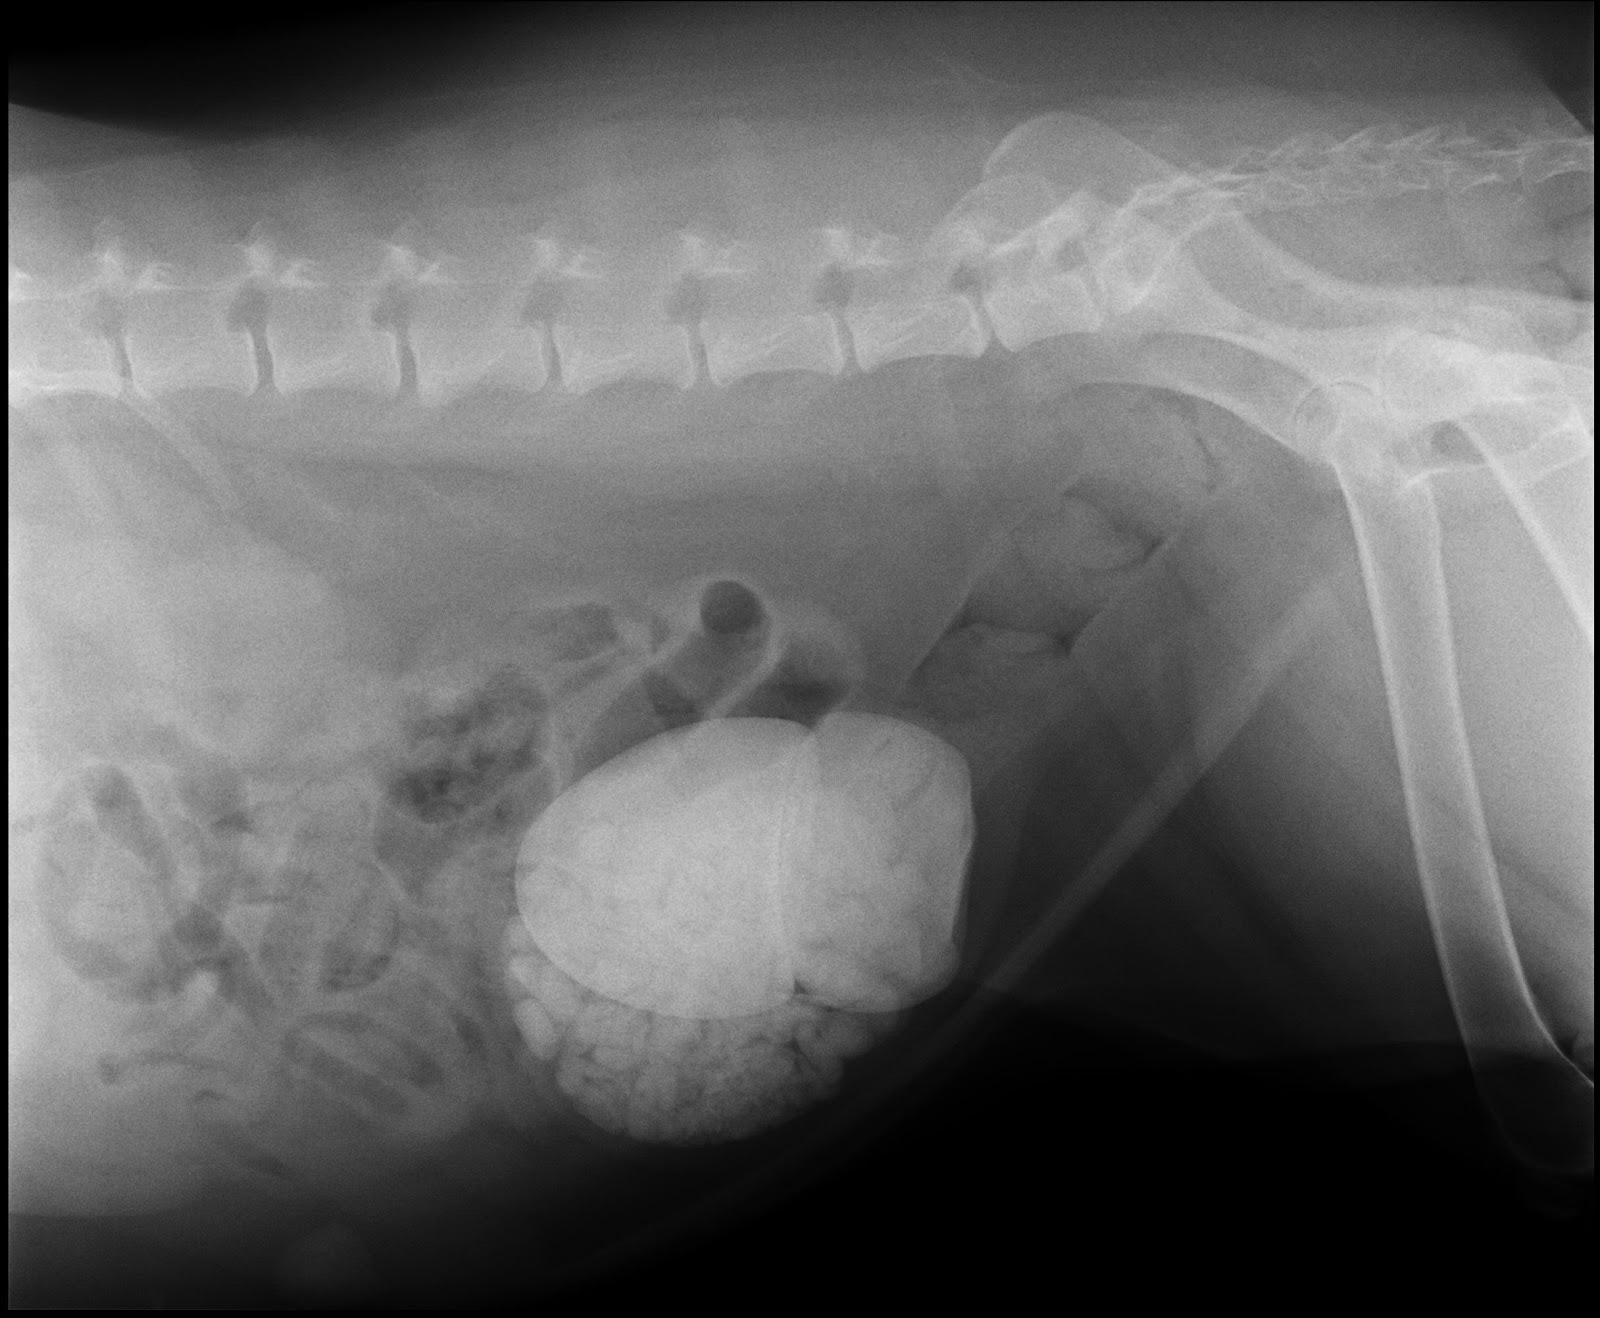

And holy cow, it's no wonder the poor dog is peeing blood. And no antibiotic is gonna fix THIS:

So she goes in for surgery Wed to get

that taken care of. For reference, this is a 113 pound dog. For those

who don't know what you're looking at, those big white spots are

stones in the bladder. That's one stone the size of an orange,

one the size of a lemon, and a whole double fistfull of gravel sized

stones.